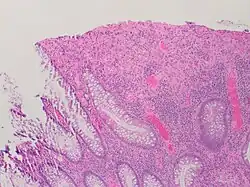

An important investigation in the assessment of colitis is biopsy for histopathology. A very small piece of tissue (usually about 2mm) is removed from the bowel mucosa during endoscopy and examined under the microscope by a histopathologist. A biopsy report generally does not state the diagnosis, but should state any presence of chronic colitis, give an indication of disease activity, as well as state the presence of any epithelial damage (erosions and ulcerations).[6]

Histopathology findings generally associated with chronic colitis include:[6]

Crypt degeneration -

Crypt branching and other architectural distortions -

Paneth cell (pictured) or gastric metaplasia (only applies in the left colon and rectum)

Other findings include basal plasmacytosis and mucin depletion.[6] Histopathology findings generally associated with active colitis include:[6]

-

Neutrophilic cryptitis (neutrophils within crypt epithelium) -

Crypt abscesses (luminal neutrophilic aggregates) -

Gland destruction -

Ulceration (seen here as absence of epithelium, and granulation tissue with many fibroblasts)